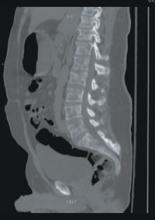

A stat CT of the patient’s abdomen and pelvis revealed no signs of obstructive uropathy to explain his acute renal failure. A sagittal CT reconstruction in bone windows of the initial ED radiological workup was revealing (FIGURE 1).

FIGURE 1

Sagittal CT reconstruction of thoracolumbar spine

The sagittal CT reconstruction in bone windows of the thoracolumbar spine (FIGURE 1) revealed multiple lucent foci throughout the osseous structures, with an anterior compression deformity of the L2 vertebral body. A subsequent skeletal survey showed a diffuse salt and pepper pattern affecting most of the osseous structures, with additional lytic lesions in the calvarium and extremities.